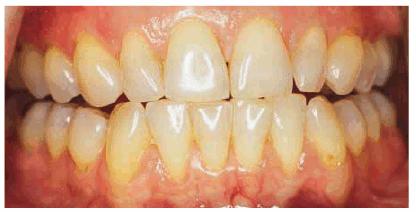

months of nightly treatment (Figures 16-18A, and 16-18B).48 Tetracycline

staining may take anywhere from 2 to 12 months of nightly treatment.49

Figure 16-18A: Years of pipe smoking have caused the extrinsic nicotine stain to become intrinsic.

Figure 16-18B: Whitening, using at-home treatment of 10% carbamide peroxide in a custom-fitted tray, was necessary to remove the stubborn nicotine stains.